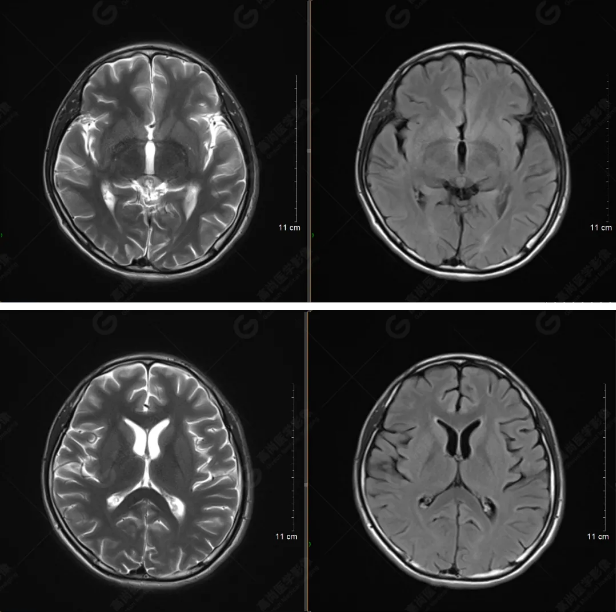

以下是平掃T2WI及FLAIR序列:

雙側(cè)大腦半球?qū)ΨQ,灰白質(zhì)對比正常,顱內(nèi)未見異常信號影。腦室系統(tǒng)未見擴(kuò)大,中線結(jié)構(gòu)居中。腦溝、裂未見增寬。幕下小腦、腦干未見異常。矢狀位示垂體形態(tài)、大小級信號未見異常。所示左側(cè)乳突內(nèi)見多發(fā)短T1長T2信號影。

顱腦MRI平掃未見明顯異常,左側(cè)乳突內(nèi)積血,建議補(bǔ)充SWI檢查。(左側(cè)為薄層原始圖像,右側(cè)為后處理5mm圖像)